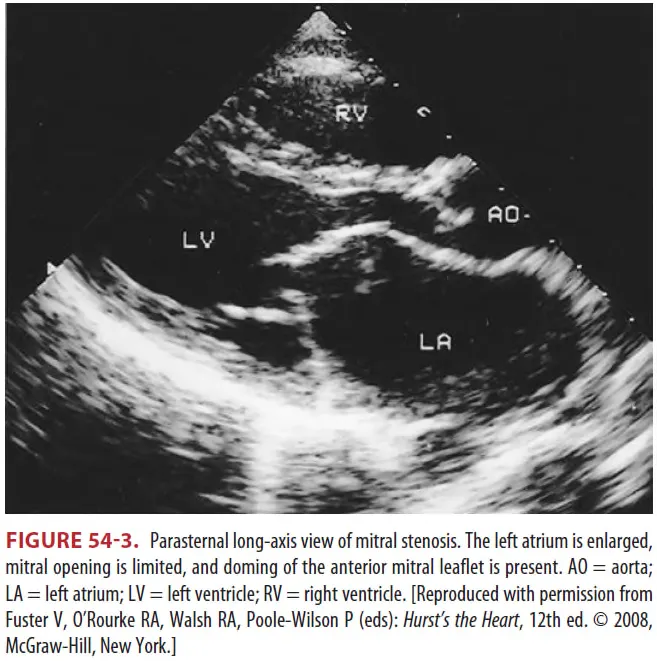

① Transesophageal echocardiography (Fig 54-3)

② Mitral valve regurgitation degree, left atrial thrombus 존재 평가